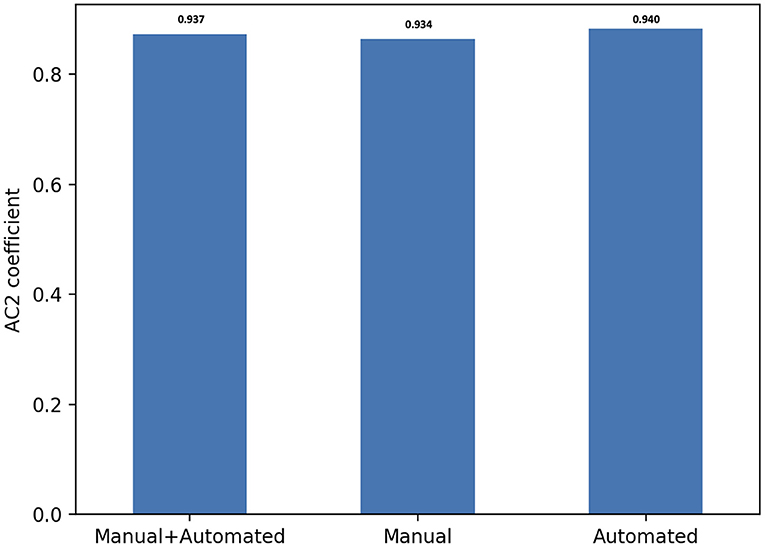

The inter-observer agreement for manual and automated contours was also investigated using Gwet's AC2 agreement coefficient with ordinal weighting.

Overall, there was substantial inter-observer reliability for quality scoring of both manual and automated contours (AC2 = 0.937, 95% CI, (0.935–0.939)). In particular, the score agreement between all raters for automated contours was significantly better than for the manual segmentation (AC2 = 0.940, 95% CI, (0.937–0.943) and AC2 = 0.934, 95% CI, (0.931–0.937), respectively, p = 0.006).

All AC2 values were qualified as very good using the probabilistic benchmark procedure, with 100% membership probability for the interval 0.8–1.0. The inter-observer agreement for each method of contouring is shown in Figure 4.

Figure 4. Score agreement between all raters for manual, automated contours and both segmentation methods. The interobserver reliability is expressed using Gwet's second-order agreement coefficient with ordinal weighting applied (AC2) (y axis).